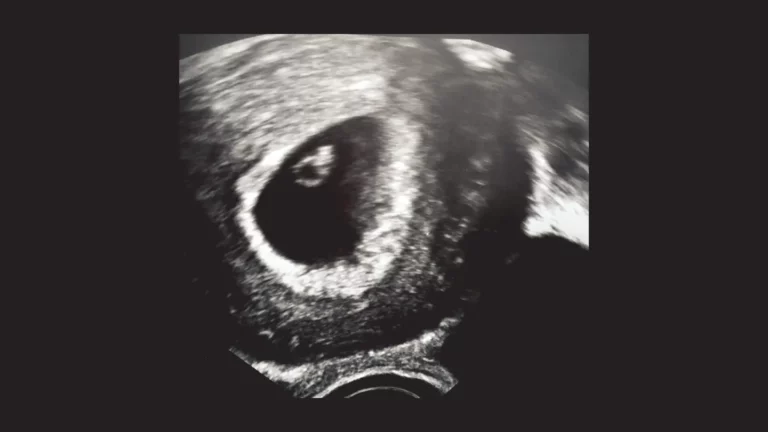

Was du wissen solltest, wenn du dein Baby verloren hast

Der Verlust eines Kindes in der Schwangerschaft ist eine der schmerzhaftesten Erfahrungen betroffener Eltern. In dieser schweren Zeit können Informationen über deine Rechte, medizinische Möglichkeiten und Unterstützungsangebote eine Hilfe sein.